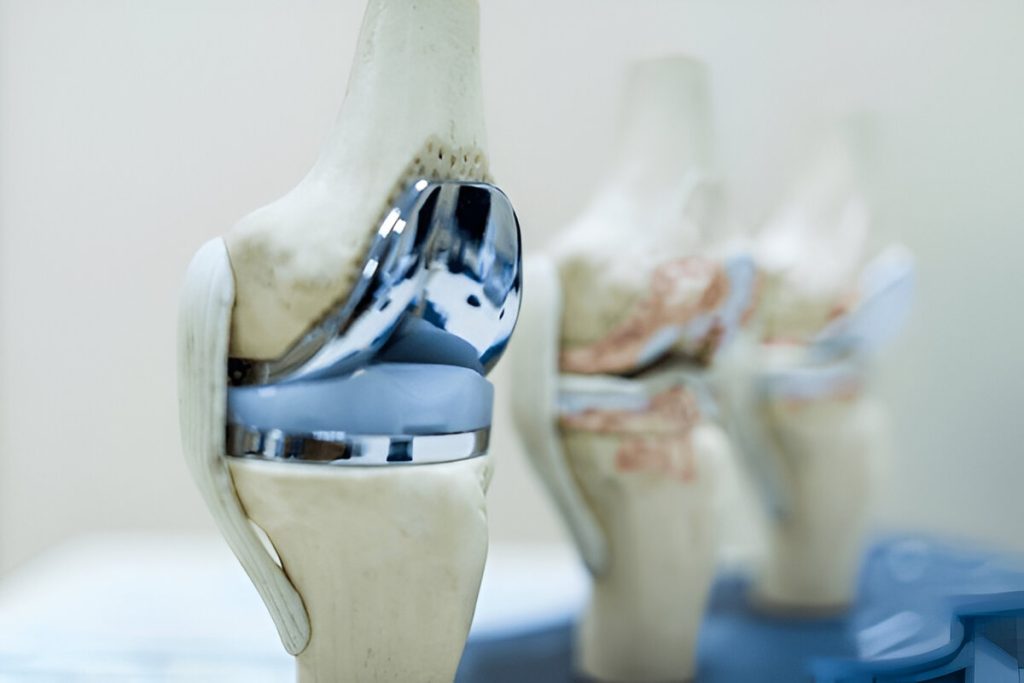

Understanding Knee Anatomy

The knee is one of the most powerful and intricate joints in the human body. It supports your weight, absorbs shock, and enables a wide range of motion. Whether you’re a professional athlete or just climbing stairs, your knees are constantly at work.

The Bones of the Knee

• Femur (thighbone) – Connects the hip to the knee.

• Tibia (shinbone) – Supports the body’s weight below the knee.

• Patella (kneecap) – Protects the front of the knee and improves muscle efficiency.

These bones articulate at the tibiofemoral and patellofemoral joints.